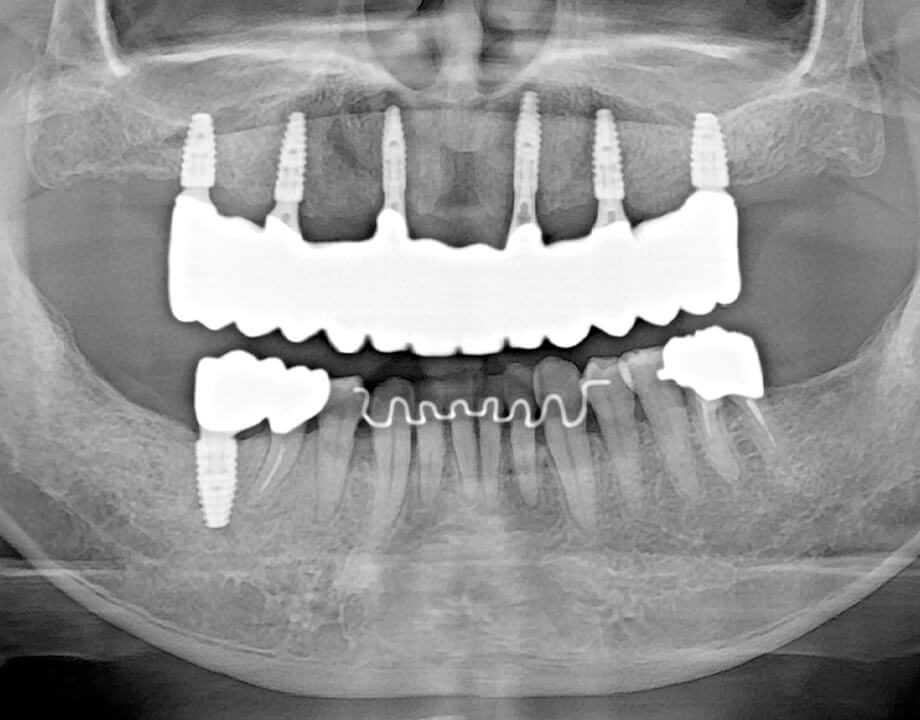

Case 07咬合再構成

アナログワックスアップ

→シュミレーション(ノーベルガイド)

→プロビジョナル(即時荷重)

→最終補綴物(ハイブリッドクラウン)